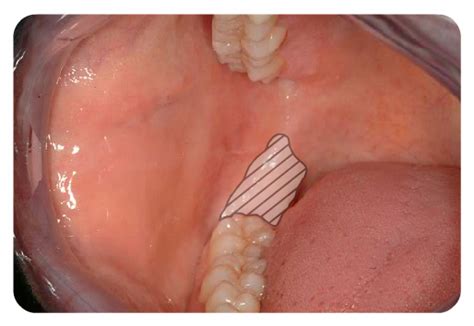

Demonstration of buccal advanced flap technique [14] | Download ...

337x264

ResearchGate

Tissue ablation with Nd:YAG laser. a. Oral mucosa covering dental ...